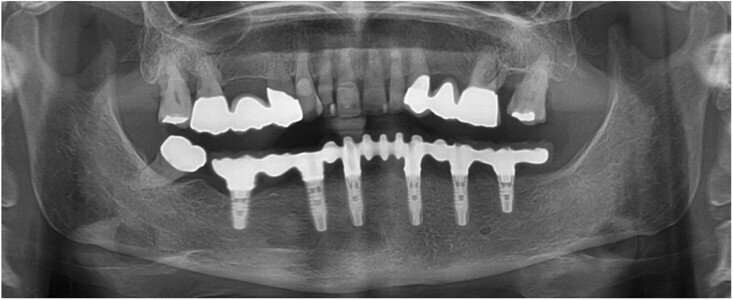

Fig. 15: Panoramic radiograph at delivery of the final CAD/CAM FDP.

Fig. 16: Panoramic radiograph at the 12-month recall appointment.

All six implants osseointegrated successfully without complications. After six months of the patient wearing the provisional FDP, a conventional impression was taken (screw-retained impression copings, open-tray technique, polyether material) to fabricate the final FDP on a new, precise cast (Fig. 11), which was then digitised with a laboratory scanner (Deluxe scanner, Open Technologies). The final framework was designed with straight connection to the implant platforms and with a cutback allowing for the veneering material (Figs. 12a & b). While the cobalt– chromium framework was fabricated using CAD/CAM technology (exocad, exocad; M1 Wet, Zirkonzahn), the veneering was performed manually, allowing for individual characterisation of the teeth (Figs. 13a–d). The models were fabricated with a laser stereolithography printer (XFAB) using an ABS-like polymer (Precisa RD096B, DWS). Healthy mucosal conditions were present at the delivery of the final CAD/CAM restoration, made from cobalt–chromium and composite veneering material (Figs. 14a–e). The accurately fitting FDP was attached with screws at 25 Ncm and the screw access area covered with composite material. The panoramic radiograph on the day of delivery showed optimal prosthetic and osseous conditions (Fig. 15). The patient followed a regular maintenance programme at the dental hygienist twice a year.

At the one-year follow-up appointment, healthy mucosal and stable crestal peri implant conditions were observed (Fig. 16). The patient was very pleased with the aesthetic and functional outcome. Thus, the performed treatment was successful, and it showed stable results without complications or the need for maintenance service after the first year.